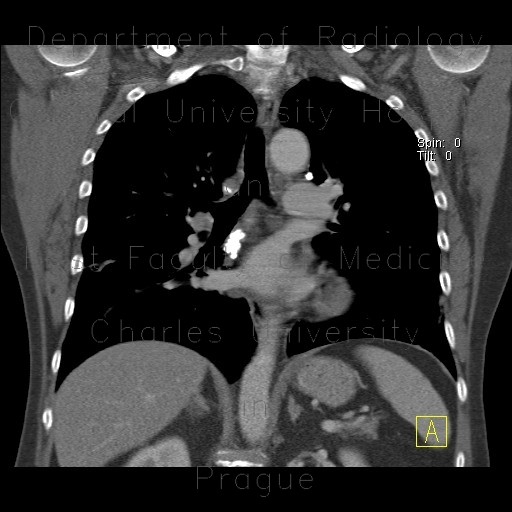

M/21

Incidental detected mass